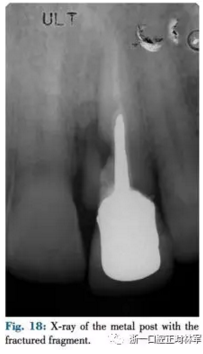

患者為一名57歲高加索人,左上中切牙受傷(圖17,18),近中唇側(cè)探診9mm,唇側(cè)探診5mm。X片提示根折及骨缺損。由于美學(xué)效果差因此不采用冠延長(zhǎng)術(shù),此外由于其冠根比較差不采用牽引及修復(fù)治療。